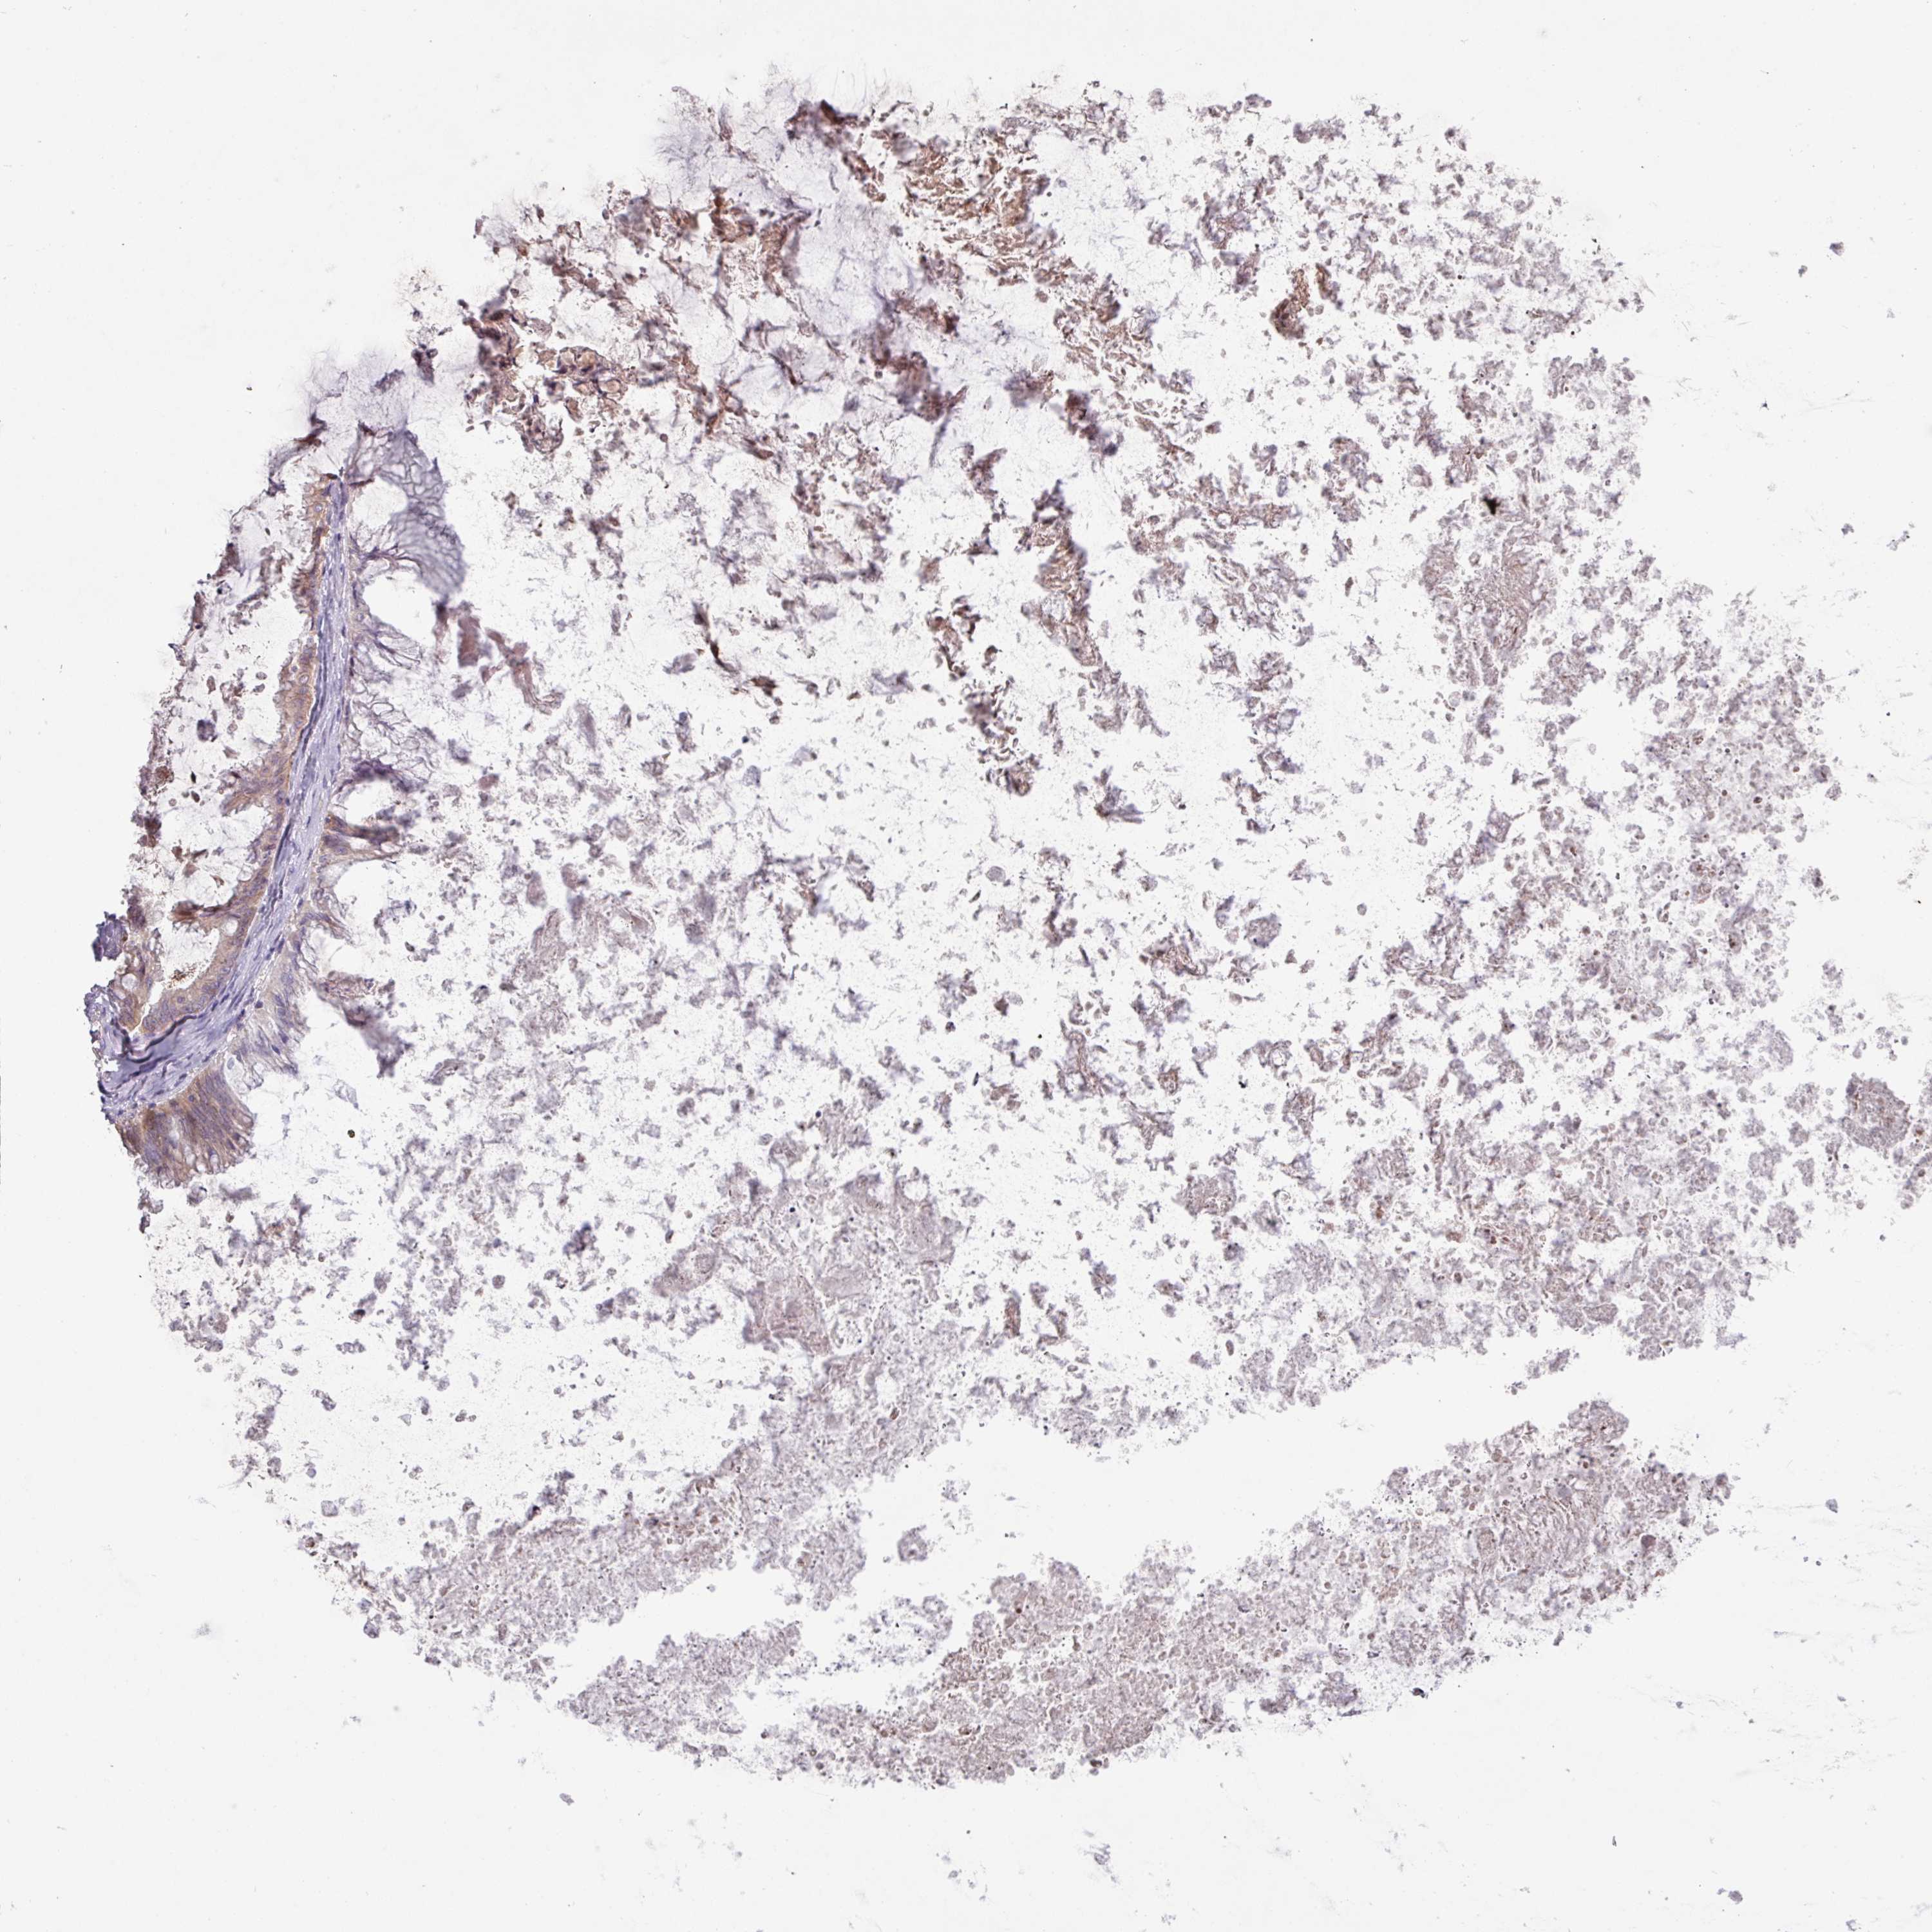

OVARIAN CANCER - Protein expressioni

A mouse-over function shows sample information and annotation data. Click on an image to view it in a full screen mode. Samples can be filtered based on level of antibody staining by selecting one or several of the following categories: high, medium, low and not detected. The assay and annotation is described here.

Note that samples used for immunohistochemistry by the Human Protein Atlas do not correspond to samples in the TCGA dataset.

Antibody stainingi

Antibody staining in the annotated cell types in the current human tissue is reported as not detected, low, medium, or high, based on conventional immunohistochemistry profiling in selected tissues. This score is based on the combination of the staining intensity and fraction of stained cells.

Each image is clickable and will lead to virtual microscopy that enables deeper exploration of all samples and also displays staining intensity scores, fraction scores and subcellular localization as well as patient and tissue information for each sample.

Antibody HPA052014

Cystadenocarcinoma, serous, NOS

Carcinoma, NOS

Cystadenocarcinoma, mucinous, NOS

Carcinoma, endometroid